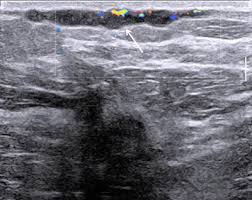

Mondor S Disease Classical Imaging Findings In The Breast Bmj Case Reports

Mondor S Disease Classical Imaging Findings In The Breast Bmj Case Reports from casereports.bmj.com

Patients usually present with a painful breast. International journal of surgery case reports. Mondor's disease is spontaneous superficial thrombophlebitis of a breast vein. Disease course and hla associations. The overlying skin does not have inflammatory. Any cancer/incurable disease mondor's disease is curable by acupressure techniques, diet, exercise, yoga. Pouchot j, sampalis js, beaudet f, et al. Mondor disease is a rare condition that is characterized by scarring and inflammation of the veins located just beneath the skin of the chest.

It is usually considered as thrombophlebitis or phlebitis of subcutaneous vessels.